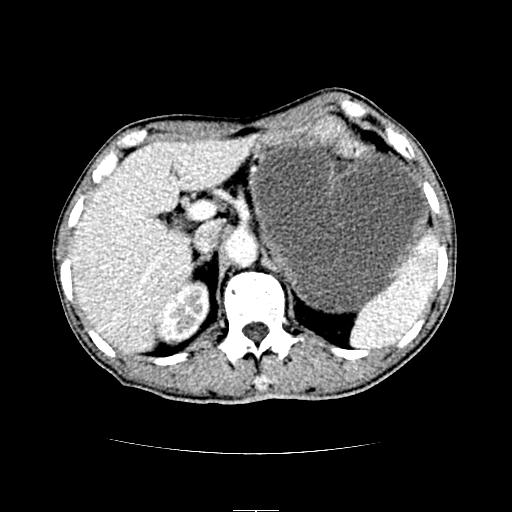

左上腹胃、脾及胰腺间巨大囊性占位性病变,内见多数薄隔,有轻度强化,明显占位效应,胰腺及左肾结构清楚,明显向后下方推压 移位。左肾见一小囊肿.多考虑:1 网膜巨大囊肿。2 左肾小囊肿。

1胃脾胰之间一巨大囊性影,胃明显向前推移,胰体尾部似肥大,考虑囊性影来源于胰腺(假性囊肿?)2左肾小囊肿。

左上腹囊性占位,虽与胰腺分界不清,胰尾似乎受压前移,病灶最大截面并不在胰腺水平,考虑来源于网膜可能性大吧,应再详细追问病史.